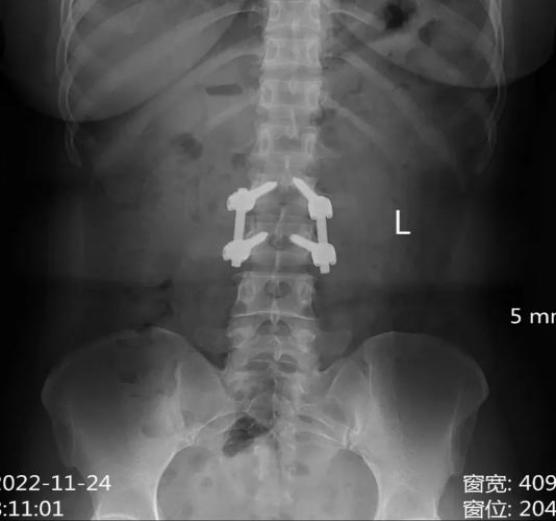

DR检查(数字化X射线摄影)

DR是传统X光片的升级版,其采用数字化技术,成像更清晰,检查更便捷。

【技术特点】

1.成像速度快:检查过程只需几分钟,适合急诊或大规模筛查。

2.辐射剂量低:DR的辐射量远低于CT,安全性较高。

3.二维平面图像:提供的是平面影像,适合观察骨骼、肺部等结构。

4.成本较低:检查费用相对便宜,适合常规体检。

【适用场景】

●骨折诊断:如四肢、脊柱、胸骨等部位的骨折。

●肺部疾病筛查:如肺炎、肺结核、肺气肿等。

●常规体检:如胸部X光片,用于初步筛查疾病。